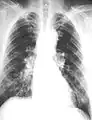

The abnormal chest x-ray and its interpretation remain the most important factors in establishing the presence of pulmonary fibrosis.[11] The findings usually appear as small, irregular parenchymal opacities, primarily in the lung bases. Using the ILO Classification system, "s", "t", and/or "u" opacities predominate. CT or high-resolution CT (HRCT) are more sensitive than plain radiography at detecting pulmonary fibrosis (as well as any underlying pleural changes). More than 50% of people affected with asbestosis develop plaques in the parietal pleura, the space between the chest wall and lungs. Once apparent, the radiographic findings in asbestosis may slowly progress or remain static, even in the absence of further asbestos exposure.[23] Rapid progression suggests an alternative diagnosis.

Extensive fibrosis of pleura and lung parenchyma. -

61 yr old working industrially with asbestos for decades.